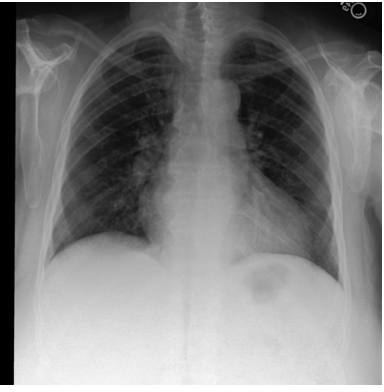

In Figure 3 we also visualize the output of Grad-CAM [20] method on the GlobalView model to highlight the importance of the localization, while the prediction of Enlarged Cardiac Silhouette was correct, the GlobalView model was focused on the lungs. Our method was able to provide accurate localization information as well as the finding.

Refer to caption

(a)

(b)

(c)

Figure 3: An example image from our dataset with enlarged cardiac silhouette. The GlobalView network detects this label correctly, but as the Grad-CAM activation map shows (b), the attention of the network is not on the cardiac region. Our method detects the finding in the correct bounding box (c).

This approach accurately detects any of the nine studied abnormalities and places it in the correct bounding box in the image. The 18 pre-specified bounding boxes are devised to map to the anatomical areas often described by radiologists in chest X-ray reports. As a result, our method provides all the necessary components for composing a structured report. Our vision is that the output of our trained model, subject to expansion of the number and variety of findings, will provide both the finding and the anatomical location information for both downstream report generation and other reasoning tasks. Despite the difficulty of localized disease detection, our method outperforms a global classifier. As our data shows (See Figure 3), global classification can be unreliable even when the label is correct as the classifier might find the correct label for the wrong reason at an irrelevant spot.